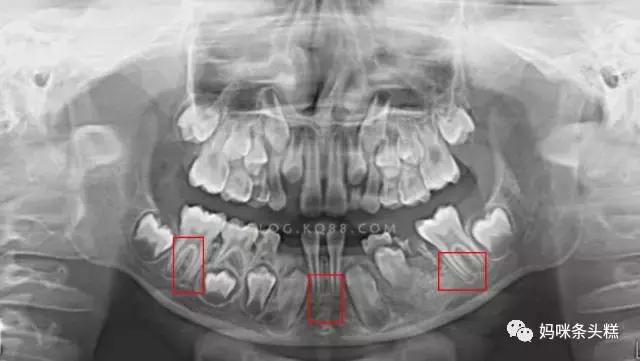

在遇到这类问题时,医生会选择给宝宝拍片,确定埋伏在牙床中未萌出的恒牙到底遭遇了什么情况。

比如这张影像就是典型恒牙先天缺失,这类情况也就无法期待恒牙萌出,解决方案就只能考虑今后在缺口位置安装代替牙来解决。

有的并不是恒牙缺失,但恒牙萌出角度偏差,又遇到相邻牙齿的阻力导致无法萌出,这时需要根据牙齿与牙齿间的间隙空间情况,决定是否需要拔除阻生牙齿,让恒牙正常萌出。